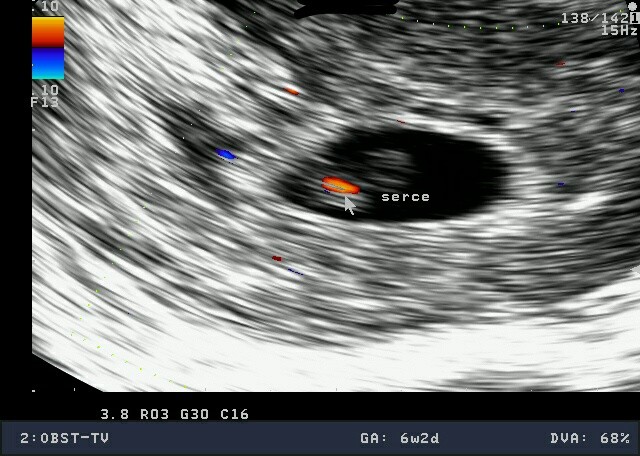

MOJE 2.5cm szczęścia!!!!!!!!